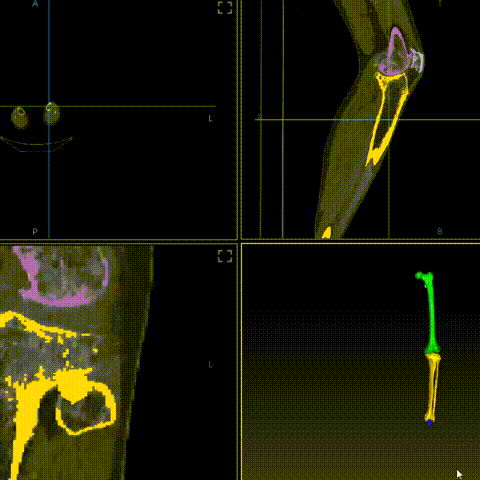

嘉奧科技開發(fā)的第一代骨科手術(shù)機(jī)器人,主要應(yīng)用于脊柱手術(shù)領(lǐng)域。從完成的臨床數(shù)據(jù)看,產(chǎn)品各項(xiàng)性能及臨床指標(biāo)均優(yōu)于國內(nèi)外同類產(chǎn)品。該設(shè)備可以實(shí)現(xiàn)脊柱手術(shù)全流程智能化,配備了術(shù)前自動(dòng)規(guī)劃、術(shù)中實(shí)時(shí)3D導(dǎo)航、輔助手術(shù)路徑等創(chuàng)新技術(shù),系統(tǒng)精度官方檢測(cè)更是高達(dá)0.9毫米以下,領(lǐng)先于國內(nèi)同類產(chǎn)品,即便與跨國企業(yè)的同類產(chǎn)品也表現(xiàn)出強(qiáng)勁的競(jìng)爭力。

作為國內(nèi)首款全國產(chǎn)化、超小型骨科手術(shù)機(jī)器人,增加了多模態(tài)影像構(gòu)建系統(tǒng)、自動(dòng)影像分割技術(shù)、骨科智能規(guī)劃系統(tǒng)、實(shí)時(shí)多維度跟蹤工具等多項(xiàng)創(chuàng)新智能化功能的同時(shí),還顛覆傳統(tǒng)手術(shù)機(jī)器人體積交大的劣勢(shì),大幅度減小了整體設(shè)備的體積與重量;此外,公司自行研發(fā)的雙目視覺定位儀與機(jī)械臂更是降低制造成本70%以上,極大加強(qiáng)了產(chǎn)品的競(jìng)爭力,可滿足不同層級(jí)、不同地域的臨床需求。公司后續(xù)還將推出含有多模態(tài)置釘檢測(cè)系統(tǒng)、全自動(dòng)化置釘系統(tǒng)等突破性技術(shù)的手術(shù)機(jī)器人產(chǎn)品。

此外,嘉奧科技研發(fā)出了新一代智能脊柱導(dǎo)航手術(shù)機(jī)器人,它采用自主開發(fā)的光學(xué)定位儀和機(jī)械臂,替代進(jìn)口產(chǎn)品,短期內(nèi),嘉奧科技將推進(jìn)智能脊柱導(dǎo)航手術(shù)機(jī)器人的臨床試驗(yàn),使其盡快進(jìn)入市場(chǎng)。

嘉奧科技智能脊柱導(dǎo)航手術(shù)機(jī)器人